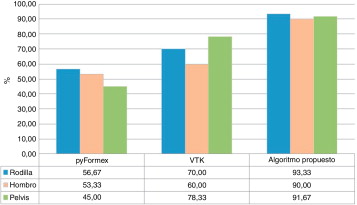

La figura 6 muestra los valores porcentuales obtenidos por cada uno de los algoritmos al determinar correctamente las estructuras anatómicas. Como se puede observar, el algoritmo propuesto obtuvo mayor índice de éxito.

|

|

|

Figura 6. Valores porcentuales obtenidos por cada uno de los algoritmos analizados. |

Según estos resultados, pyFormex es más rápido, pero su utilización implica la no obtención de una correcta descomposición del modelo geométrico. Sin embargo, los tiempos de procesamiento de VTK y el algoritmo propuesto son similares, y este último ofrece mejores resultados en cuanto a la descomposición geométrica.

El algoritmo, bajo las mismas condiciones y en un corto tiempo de procesamiento, define el dominio geométrico de estructuras óseas con resultados superiores a los obtenidos mediante el empleo de VTK y pyFormex, con un nivel de confianza estadístico del 90% para el total de los casos analizados.